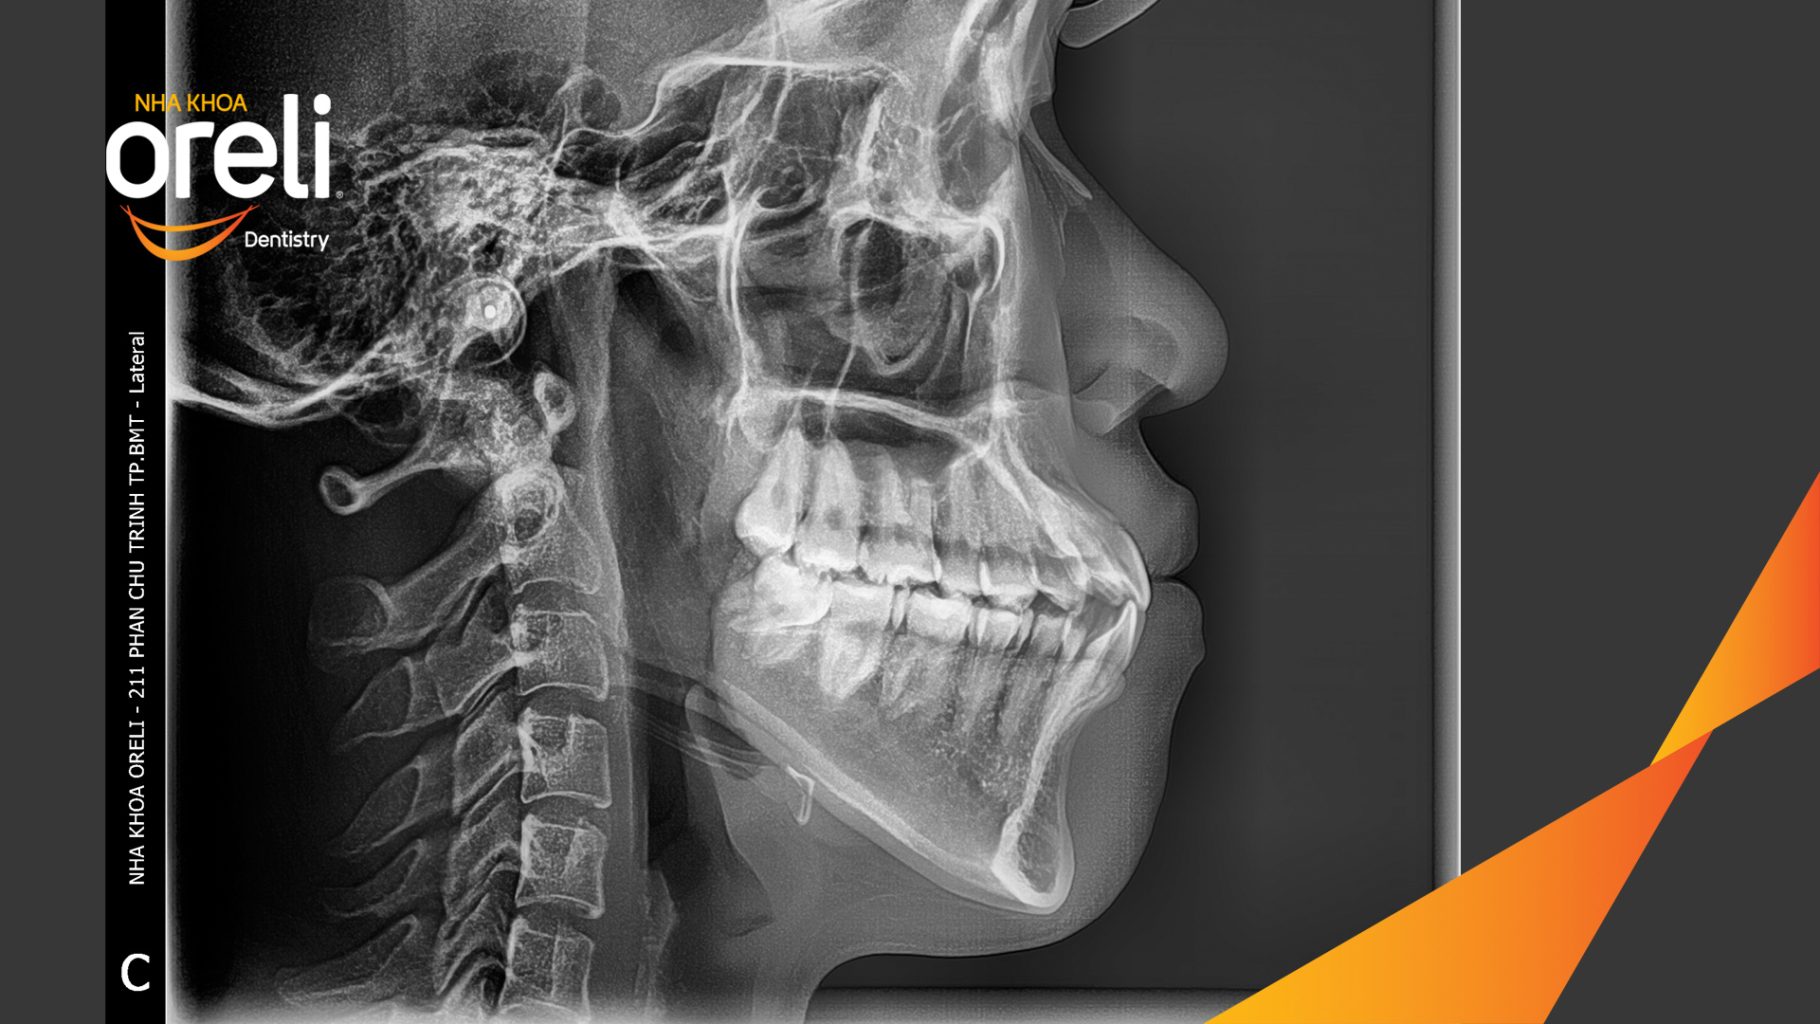

Hành trình thay đổi nụ cười ca lệch khớp cắn hạng 3, hàm dưới trượt ra trước và nhô xương hai hàm.

Tình trạng này không chỉ ảnh hưởng đến thẩm mỹ khuôn mặt mà còn gây khó khăn trong ăn nhai và phát âm. Thông qua quá trình niềng răng được cá nhân hóa, khách hàng đã từng bước cải thiện khớp cắn và lấy lại sự tự tin trong giao tiếp.